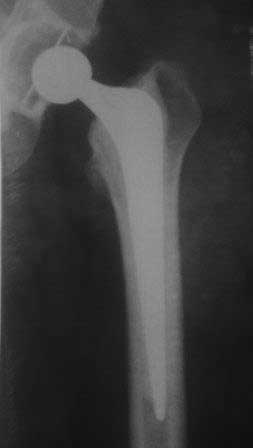

Уважаемые коллеги. Обратилась наша коллега, 1964 г.р. В 2008 году перенесла тяжелый анафилактический шок (гемодез), получила большие дозы гормонов, через 6 месяцев развился асептический некроз головок обеих бедренных костей.

В апреле и июле 2009 года было произведено эндопротезирование обеих т/б суставов в ТашМИ., с тех пор беспокоият боли в правой ноге, особенно сильно стартовые боли - первые шаги, потом боль уменьшается, но не исчезает, сильно хромает, долго ходить не может, постоянно употребляет НПВС. В последнее время боли усиливаются, боли в основном в паховой области и медиальнее в глубине, а также на уровне с/з диафиза бедра. Левая нога не беспокоит. Очень просит помощи. Уважаемые коллеги, как можно ей помочь? В крайним случае согласна и на реимплантацию! Или может быть есть более щадящие и недорогие методы.